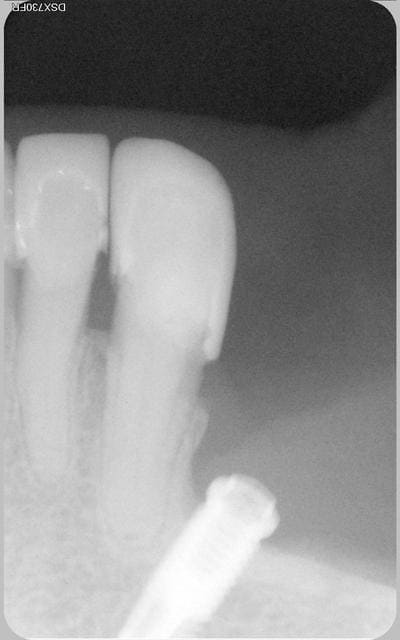

La patiente revenait de l'implantologiste. Je fais une radio de control et je vois ca. La patiente refusait toute prothèse.

Voilà le bébé

La patiente est revenue pour un soin a faire sur 35 qui est bien vivante.

Satisfaite de son coeff masticatoire.

cela fait excactement 9 ans, que l'implant a été posé.

Bien sur et c'est évident que le confrére implanto ne ferait plus ca maintenant.

La nature a bon dos parfois